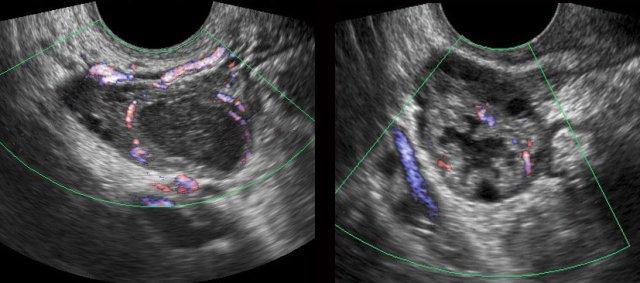

PID ca lâm sàng 3

Phụ nữ trẻ với đau hố chậu phải cấp tính và CRP 140.

Siêu âm bụng hoàn toàn bình thường.

TVUS cho thấy hình ảnh tăng sinh mạch máu nhẹ ở cả hai vòi trứng và buồng trứng, được bao quanh bởi mô mỡ tăng âm, ép xẹp vừa phải (*).

Đây là hình ảnh của mô mỡ phúc mạc, mạc treo và mạc nối bị viêm nhẹ.

CT xác nhận ruột thừa bình thường (mũi tên) và hình ảnh tăng tỷ trọng lan tỏa nhẹ của mỡ phúc mạc, mạc treo và mạc nối (*).

Bệnh nhân hồi phục nhanh chóng với kháng sinh. Cấy vi khuẩn và PCR đều âm tính.